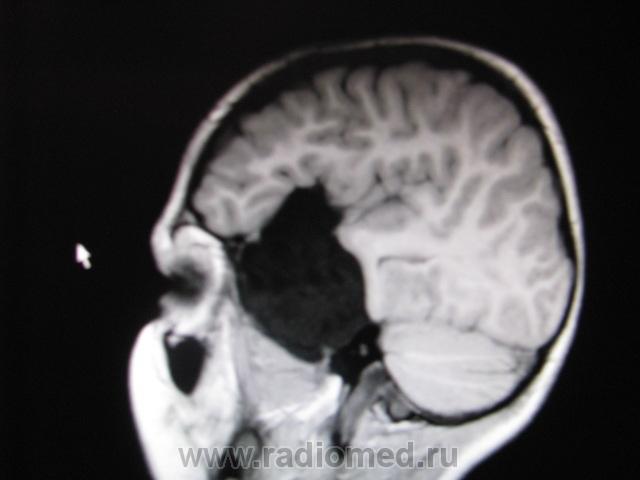

Крупная арахноидальная киста правой височной области.

да, до этого мальчик жалоб не предъявлял. наверное киста увеличилась, масс-эффект на прилежащие струкутры усилился , появилась клиника.

Да, это врожденная арахноидальная киста.